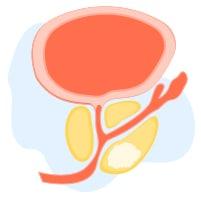

အမျိုးသားများ ဆီးကျိတ် ကျန်းမာရေး ကောင်းစေဖို့

အမျိုးသားတွေဟာ အသက်ကြီးလာတာနဲ့အမျှ ဆီးကျိတ် နဲ့ ပတ်သက်တဲ့ ပြဿနာတွေ ဖြစ်နိုင်ခြေများလာလေ့ရှိပါတယ်။ ဆီးကျိတ်ရောင်တာက စလို့ ဆီးကျိတ်ကင်ဆာအထိ အမျိုးမျိုးဖြစ်နိုင်ပါတယ်။ ဆီးကျိတ်ရောဂါလက္ခဏာတွေကို သိရှိဖို့နဲ့ ဆီးကျိတ် ကျန်းမာရေး ကောင်းစေဖို့ နေထိုင်စားသောက်နည်းတွေကို သိထားသင့်ပါတယ်။ အဖြစ်များတဲ့ ဆီးကျိတ်ရောဂါများ ဆီးကျိတ်ရောင်ရမ်းခြင်း ဆီးကျိတ်ရောင်ရမ်းတာက ဘယ်အရွယ်မှာမဆို ဖြစ်နိုင်ပေမယ့် ငယ်ရွယ်တဲ့အမျိုးသားတွေ (၃၀-၅၀ကြား)တွေမှာ ပိုဖြစ်တတ်ပါတယ်။ ဆီးကျိတ်ရောင်ခြင်းမှာ -ဘက်တီးရီးယားကြောင့် ရောင်ရမ်းခြင်းနဲ့ -ဘက်တီးရီးယားကြောင့် မဟုတ်ဘဲ တခြားအကြောင်းအရင်းကြောင့် ရောင်ရမ်းခြင်း ဆိုပြီး ၂မျိုးရှိပါတယ်။ လက္ခဏာအနေနဲ့ -ခဏခဏ ဆီးသွားချင်တာ -ဆီးကျန်တာ -ချမ်းတုန်ဖျားတာ -ဆီးပူဆီးကျဉ်တာတွေ ဖြစ်တတ်ပါတယ်။ ဆီးကျိတ်ကြီးခြင်း ကင်ဆာမဟုတ်တဲ့ ရိုးရိုးဆီးကျိတ်ကြီးခြင်းက အသက်ကြီးလေ ဖြစ်နိုင်ခြေ များလေလေပါ။ အသက် ၅၀ဝန်းကျင်ဆို အမျိုးသား၂ယောက်မှာ ၁ယောက် ဖြစ်နိုင်ခြေရှိပါတယ်။ အသက် ၆၀ကျော်လာရင်တော့ ဖြစ်နိုင်ခြေက ၇၅% ထိတက်လာပါတယ်။ လက္ခဏာအနေနဲ့ -ဆီးသွားရခက်တာ -ဆီးညှစ်ပေါက်ရတာ -ဆီးလုံးသေးတာ -ဆီးမထိန်းနိုင်တာ -ခဏခဏ ဆီးသွားချင်တာ -ဆီးကျန်ပြီး တစ်စက်စက်နဲ့ ကျနေတာတွေ ဖြစ်နိုင်ပါတယ်။ ဆီးကျိတ်ကင်ဆာ အမျိုးသားတွေ အဖြစ်အများဆုံးကင်ဆာတွေထဲမှာ ဒုတိယနေရာမှာ […]